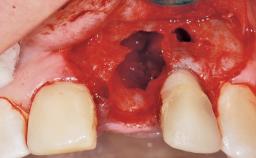

Late Flapless Placement of an Implant in a Maxillary Left Central Incisor Site

Bone Augmentation Horizontal|Staged

Augmentation Materials Xenogenous|Membrane

Soft Tissue Grafting Simultaneous